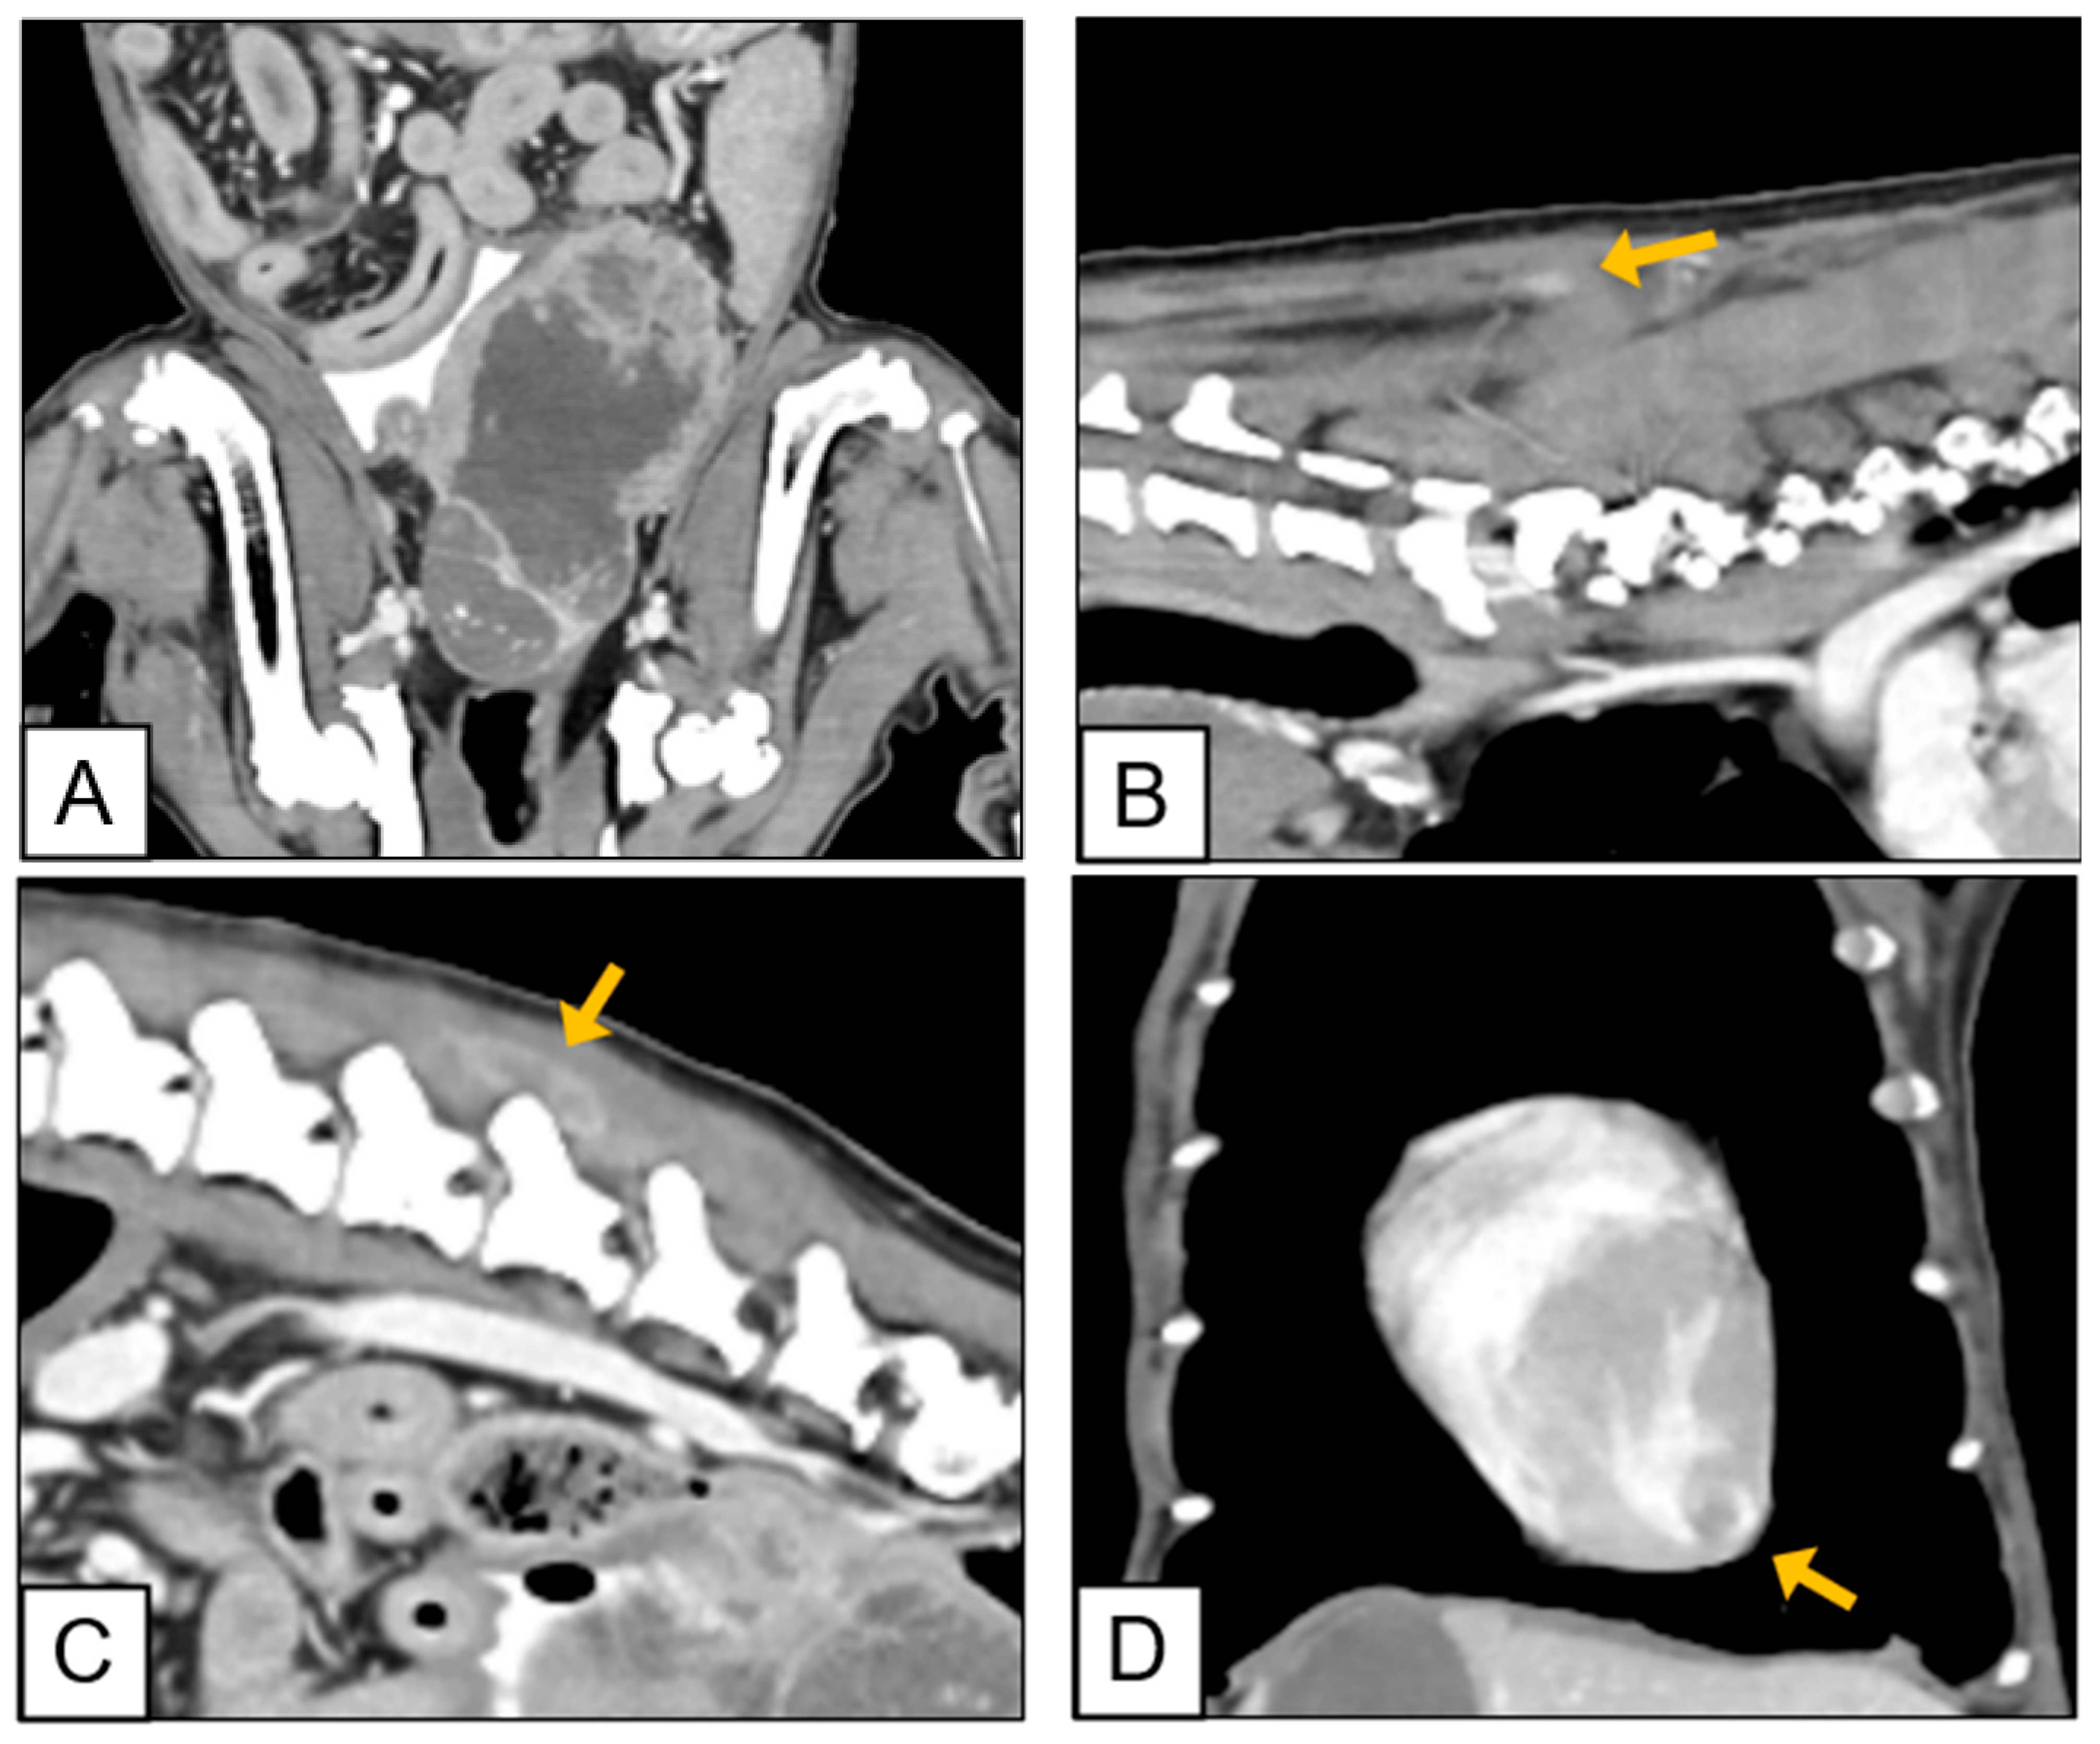

2.3. Diagnostic Imaging